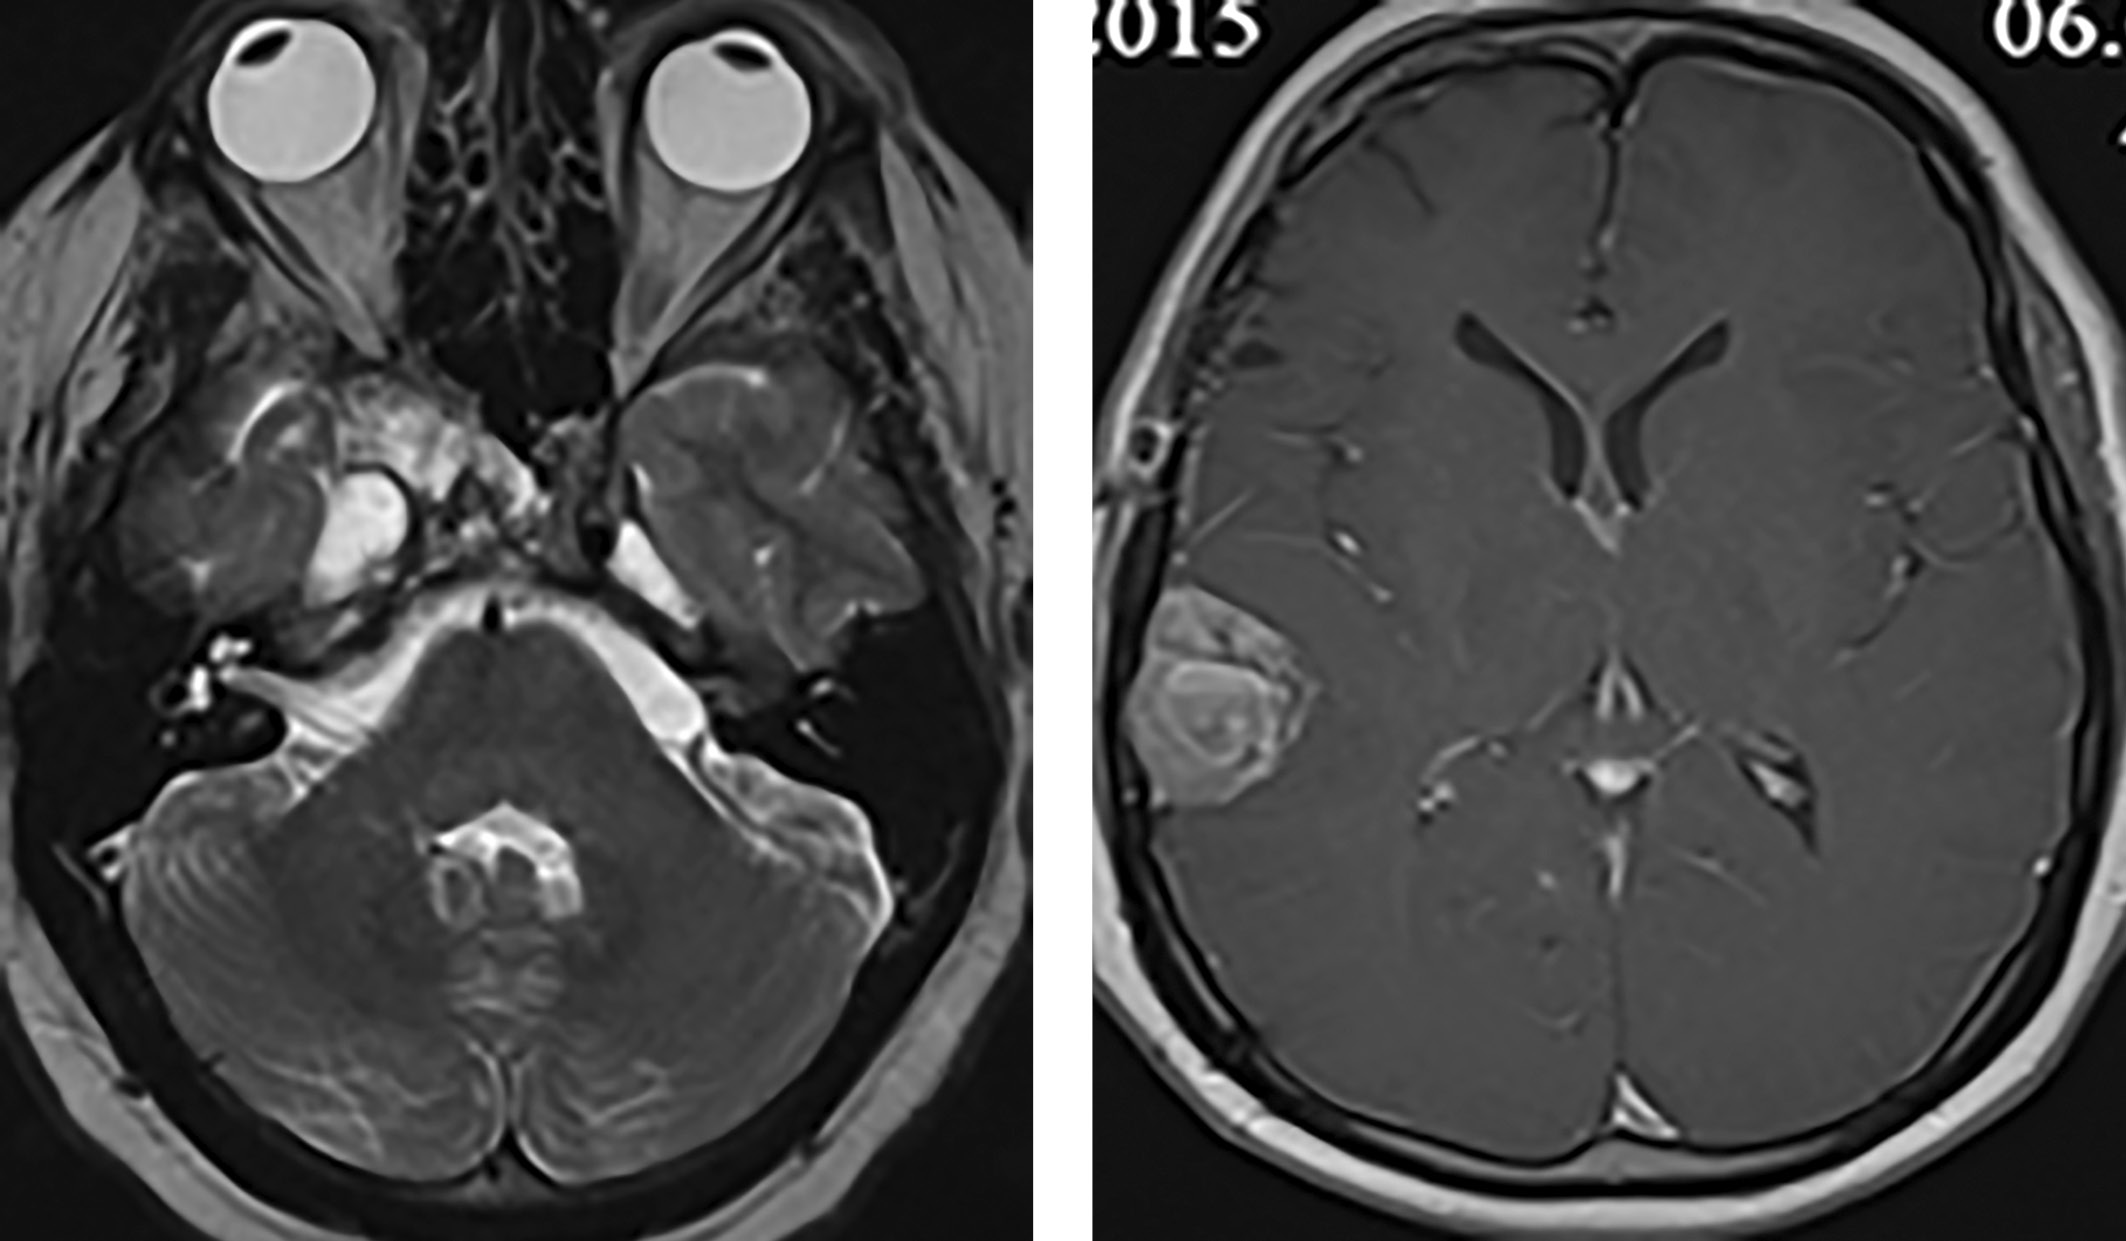

В 2015 г. в связи с появлением жалоб на головные боли было проведено МРТ-исследование головного мозга, выявившее объемные образования правой височной области и области задней поверхности пирамиды височной кости, убедительных данных за продолженный рост опухоли в области правого кавернозного синуса нет (рис. 1).

После операции отмечено снижение уровня ПРЛ до 53 538 мЕд/л, начата терапия каберголином в дозе 1 мг с постепенным повышением до 2 мг в неделю. Отмечена нормализация ПРЛ (380 мЕд/л) в августе 2016 г. По данным МРТ не отмечено продолженного роста опухоли (рис. 3).

С декабря 2017 г. к таблетированной терапии гидрокортизоном и левотироксином добавлен трансдермальный гель тестостерона. При ежегодных контрольных осмотрах с 2018-го по 2023 гг. рецидива опухоли не выявлено (рис. 4). На фоне приема каберголина 2 мг в неделю сохраняется нормопролактинемия (ПРЛ — 149 мЕд/л). Состояние пациента удовлетворительное, он самостоятельно себя обслуживает и ведет обычный образ жизни.

Рисунок 1. МРТ головного мозга пациента С. 35 лет визуализируются опухоли правой височной области и области задней поверхности пирамиды височной кости.

Риcунок 3. МРТ (январь 2016 г.) — данных за рецидив опухоли не выявлено.

Рисунок 4. МРТ (2020–2023 гг.) — не отмечено продолженного роста опухоли.